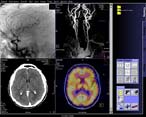

Все томографы фирмы SIEMENS объединяет единый интерфейс пользователя – syngo. Помимо стандартных закладок Examination, Viewing, Filming имеется закладка 3D с возможностями осуществлений MPR – (в реальном времени) и MIP-реконструкций.

Программно и технически (в комплект поставки вошел автоматический инъектор Medrad CT Tripak CTP-200-FLS) реализованы возможности КТ-ангиографии. Имеется опциональная программа Pulmo CT для исследования легочной эмфиземы.

Рисунок 9 – Интерфейс пользователя

Современный спиральный компьютерный томограф с длительностью спирали до 100 сек, пространственным разрешением до 0,32 мм и обеспечением отличного диагностического качества изображения (специфицированного низкоконтрастного и высококонтрастного разрешения). Двойной ряд датчиков позволяет за одно сканирование получать два среза, что значительно убыстряет время исследования. Поставляется в двух возможных вариантах: с минимальной длительностью полного 360° скана 1 сек. или 0,8 сек. Предоставляет удобство работы, эргономичность, комфорт как для пациента, так и для персонала (толщина гентри всего 56 см, интегрированный в гентри индикатор контроля за задержкой дыхания, лазерные маркеры для позиционирования пациента, встроенный в гентри монитор основных параметров сканирования) и включет в полном объеме низкодозные Сименс-технологии (UFC детектор, CARE Filter, CARE Dose, CARE Vision с HandCARE, SoftSCAN, Pediatric SCAN, Preventive CARE и пр.). Обеспечивает безопасность проведения обследований для пациента как с точки зрения минимизации лучевой нагрузки, так и с точки зрения эффективности используемых режимов сканирования.

Простота и интуитивность проведения обследования обеспечивается syngo ультимодальной программной платформой и уникально удобным пользовательским интерфейсом. Безопасность инвестиций и четкое представление о перспективах развития гарантируется непрерывным обновлением (syngoEVOLVE) программных и компьютерных модулей (при стандартной поставке – в течение 5 лет), а также возможностью модернизации сканера (Evolve программа) до более высоких технологий компьютерной томографии (меньшая длительность скана, большая длина спирали и мультисрезовая технология).

Оснащен мощными средствами трехмерной постобработки изображений. Имеет широкий набор программных и программно-аппаратных клинических пакетов для решения разнообразных диагностических задач. Позволяет проводить скрининговые обследования, виртуальную эндоскопию, перфузию, интервенции под контролем КТ, метрический анализ васкулярных структур и многое другое.